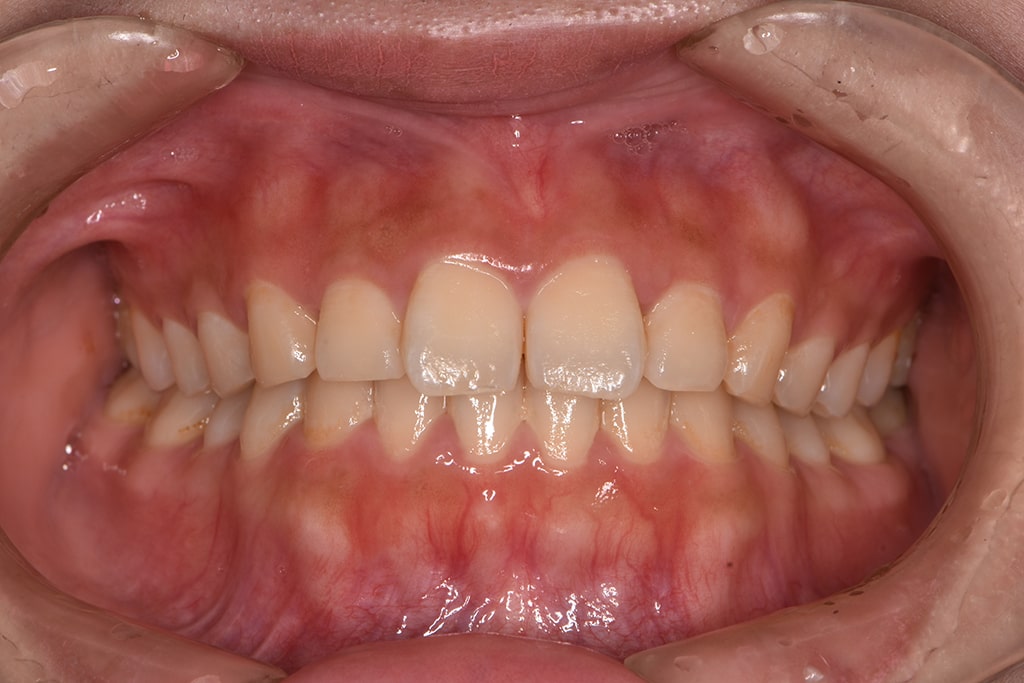

口腔内撮影

現在のお口や歯の状態を確認するために、口腔内の写真を撮影します。